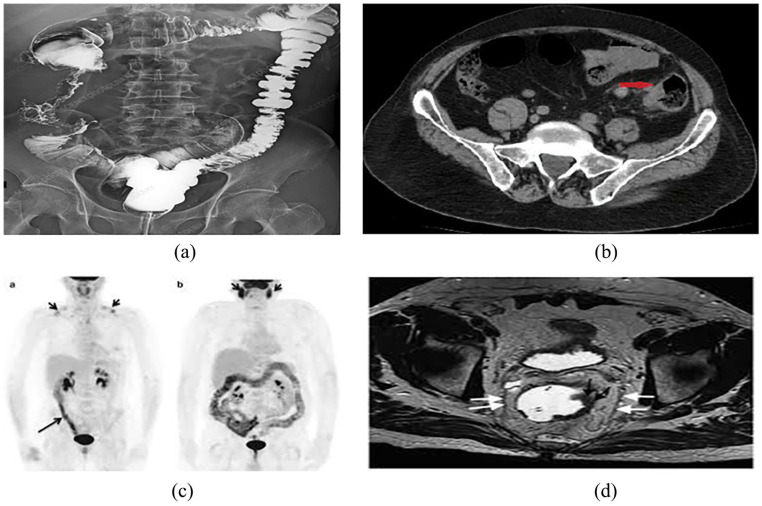

Image-based diagnosis has become a crucial tool in the identification and management of various cancers, particularly lung and colon cancer. This review delves into the latest advancements and ongoing challenges in the field, with a focus on deep learning, machine learning, and image processing techniques applied to X-rays, CT scans, and histopathological images. Significant progress has been made in imaging technologies like computed tomography (CT), magnetic resonance imaging (MRI), and positron emission tomography (PET), which, when combined with machine learning and artificial intelligence (AI) methodologies, have greatly enhanced the accuracy of cancer detection and characterization. These advances have enabled early detection, more precise tumor localization, personalized treatment plans, and overall improved patient outcomes. However, despite these improvements, challenges persist. Variability in image interpretation, the lack of standardized diagnostic protocols, unequal access to advanced imaging technologies, and concerns over data privacy and security within AI-based systems remain major obstacles. Furthermore, integrating imaging data with broader clinical information is crucial to achieving a more comprehensive approach to cancer diagnosis and treatment. This review provides valuable insights into the recent developments and challenges in image-based diagnosis for lung and colon cancers, underscoring both the remarkable progress and the hurdles that still need to be overcome to optimize cancer care.